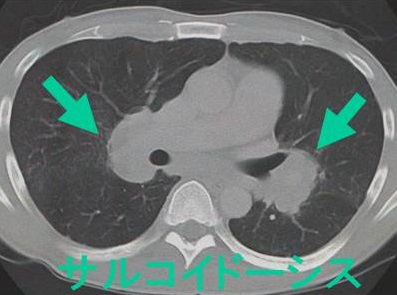

胸部CTでは他に、胸膜側のリンパ路に沿った多発粒状影や、ギャラクシーサイン(粒状影が集簇して結節を形成)を認めます。肺結核やMALTリンパ腫などでも見られます。(Sarcoidosis Vasc Diffuse Lung Dis. 2016 Oct 7;33(3):247-252.)